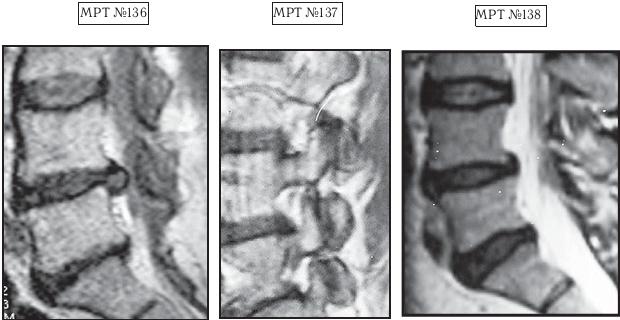

На МРТ № 136 наблюдается состояние поясничного отдела позвоночника после перенесенной ранее операции по удалению грыжи межпозвонкового диска в сегменте LV-SI (практически полное отсутствие межпозвонкового диска), а также грыжа межпозвонкового диска в сегменте LIV-LV, абсолютный стеноз спинномозгового канала, сглаженность физиологического лордоза.

На МРТ № 137 наблюдается выраженный спондилоартроз со смещением суставных поверхностей по отношению друг к другу (нарушение конгруэнтности) вследствие снижения высоты межпозвонковых дисков в сегментах LIV-LV и LV-SI и сглаженности физиологического лордоза.

На МРТ №°138 наблюдается состояние поясничного отдела позвоночника после лечения методом вертеброревитологии: отсутствие грыжи межпозвонкового диска в сегменте LIV-LV, отсутствие стеноза спинномозгового канала, восстановление физиологического лордоза. И самое главное — восстановлен полностью утраченный межпозвонковый диск в сегменте LV-SI!

Однако вначале, пожалуй, поясню, почему состояния позвоночника этой женщины значительно усложняло уже имеющиеся теоретические расчёты. Во-первых, во время операции данной пациентке практически полностью удалили межпозвонковый диск. Если внимательно рассмотрите снимок МРТ № 136, то увидите в сегменте LV-SI, лишь незначительное количество оставшихся живых клеток (фрагментов) пульпозного ядра в вентральной части бывшего диска. Во-вторых, гиалиновые пластинки значительно изменены, наблюдается тенденция к сращению смежных тел позвонков. В-третьих, имеется спондилёз и остеофиты в двух сегментах LIV—LV и LV-SI, а также гипертрофия передней связки на этом уровне. В-четвертых, пожалуй, это самый главный аргумент — наличие спондилоартроза, деформация с разрастанием дугоотростчатых суставов на уровне пораженных сегментов (МРТ № 137). А если учесть, что именно дугоотростчатые суставы служат основной опорой в выстраиваемой биомеханической конструкции по методу вертеброревитологии для оптимизации условий к активизации репаративной регенерации, то, естественно, это могло в значительной степени осложнить весь процесс восстановления межпозвонкового диска (я имею в виду в сегменте Ly — Sj) и свести на нет все теоретические расчеты.

Прежде чем приступить к данной работе, я просчитал все возможные риски и удостоверился, что грыжу межпозвонкового диска в сегменте LIV—LV я уберу в любом случае, и даже если бы у меня не получилось восстановить межпозвонковый диск в сегменте LV—SI, то это бы не усугубило здоровье данной пациентки. Должен заметить, что труд был довольно кропотливым, но результаты этой сложной работы оправдали ожидания. Поставленная задача была успешно решена: на практике мне удалось доказать свои же теоретические предположения о возможном восстановлении межпозвонкового диска даже в далеко зашедшей стадии дегенерации, то есть вывести из финальной стадии развития дегенерации межпозвонковый диск и восстановить его до полной функциональной состоятельности. Конечно, основная цель была достигнута, однако сама конструкция, на мой взгляд, была построена не совсем идеально. При восстановлении биомеханики позвоночника и создании условий для восстановления межпозвонковых дисков в сегментах LIV—LV и LV-SI мне пришлось установить позвонок LIV под небольшим углом по отношению к позвонку LV, что было обусловлено значительными изменениями (разрастаниями) дугоотростчатых суставов в данных сегментах. Но несмотря на этот эстетический нюанс, «конструкция» получилась довольно стабильная и функциональная (МРТ № 138).